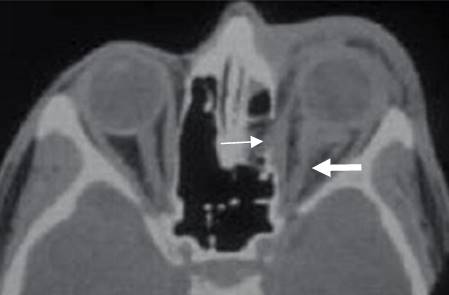

A: TAC axial y B: TAC reconstrucción coronal. Fractura en el borde interno de la órbita.

C: TAC axial en ventana de tejidos. Hay herniación de la grasa, pero permanece intacto el músculo recto interno.